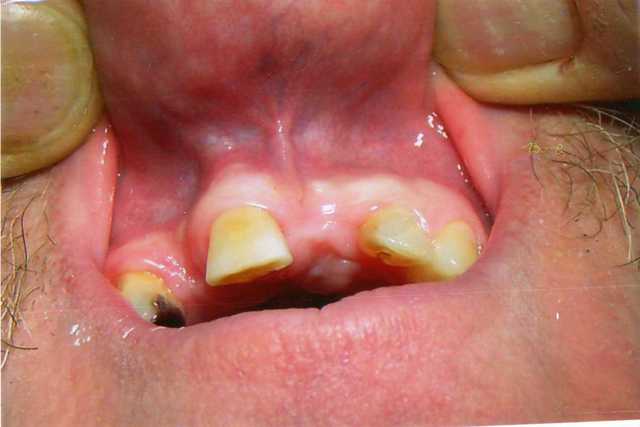

Merci Pxav de tes réponses et de faire profiter de ton expérience en la matiére.Encore un conseil... peut on envisager ces techniques d'expansion pour des édentations unitaires de ce type , sans risque de conséquences paro des dents voisines afin d'echapper soit à une greffe os et/ou conjonctif ,sachant que pour ce patient le volume osseux est suffisant pour poser:sur 12 AXIOM 3,4X12 et 4X12 sur 21 ?

Chaudron014 rmnz5b - Eugenol

Chaudron015 pob3dh - Eugenol

t'auras quand même un peu de mal...sur 12...

de tout gérer rien qu'en expansion...maintenant, rien n'interdit de faire expansion et une petite technique du roulé pour gagner un peu de volume de conjonctif...;-))

Salut Bourgogne,

pourquoi 4x12 sur 21?

la philosophie de l'Axiom est la mini invasivité, alors, 3.4 ça doit suffire.

pour donner une réponse pour 12, il me faudrait un scanner, car si le risque pour les dents adjacentes est faible, au niveau osseux, tu t'attaques à quelque chose de difficile.

N'oublie pas que l'expansion passe par la compréhension de l'os, donc avant de voir un résultat, il faut imaginer comment faire travailler toutes ces petites cellules, et où tu va réussir à les emmener.

plus c'est difficile, plus il faut répéter les gestes dans sa tête.

A vue de nez dans ton cas, il me semble que plusieurs pistes sont envisageables:

odf pour gagner un peu d'espace, pas forcement pour l'implant mais pour avoir plus d'os.

sans allez jusqu'à utiliser des ostéotenseurs, une expansion en plusieurs temps avec ou sans vitalos.

ou fracture en bois vert, avec implant immédiat ou plus tard.

j'utilise des implant coniques lisse pour préparer mes sites d'expansion, le cylindro conique (Axiom) n'est pas idéal en première intention.

mais scann indispensable et soin sur 13